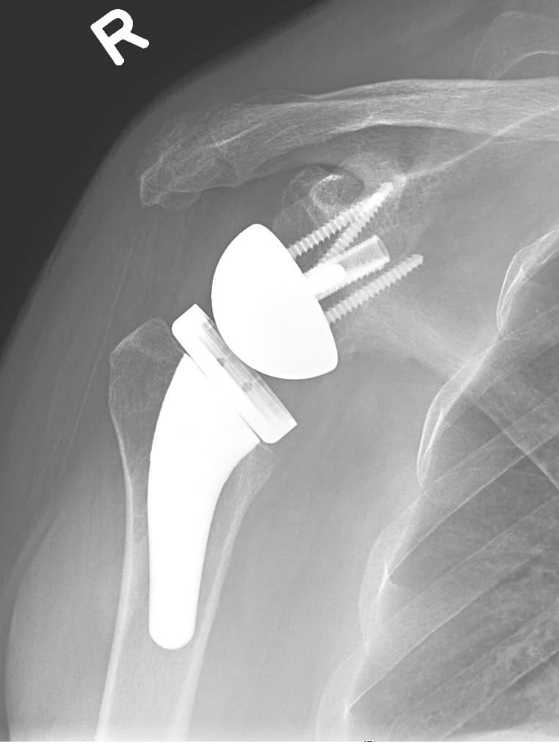

During the reverse shoulder replacement surgery, the anatomy of the shoulder is altered to the exact opposite location. The surgeon replaces the damaged humeral head with an artificial glenoid fossa, and a metal ball is placed where the original glenoid fossa was.

This placement of the artificial parts makes it possible to increase shoulder movement by using the metal ball as a fulcrum to the artificial glenoid fossa.

Choosing the right hand therapist starts with them being able to read your X-rays and then fabricate the right brace for you. The therapists at Action Rehab Hand Therapy Clinic are experienced in assessing and reading X-rays.